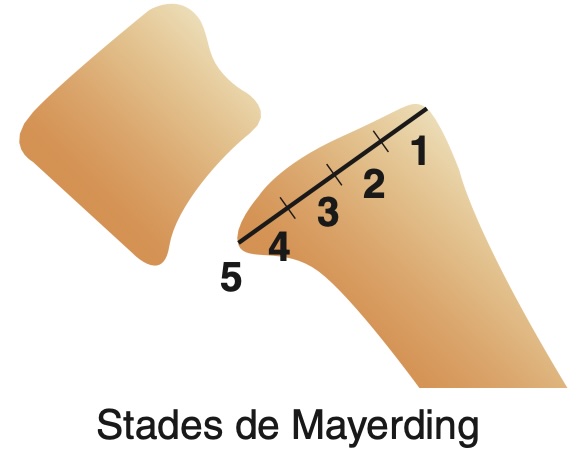

D --> L[canal étroit<br>et/ou rétréci]Le dernier disque mobile est nommé L5-S1.